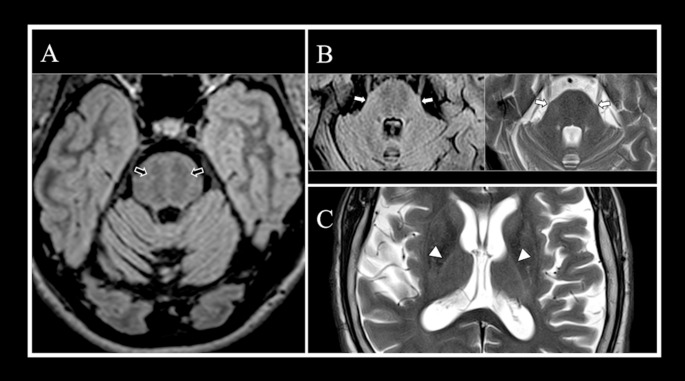

Abstract Image